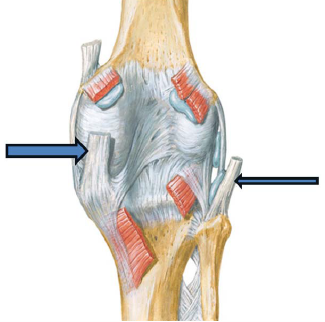

De acordo com a figura apresentada, a estrutura anatômica apontada pela seta mais fina é o

A estrutura anatômica apontada pela seta mais grossa é o